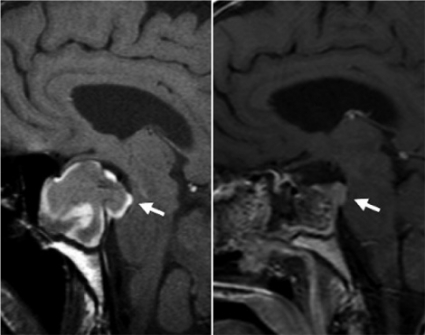

Ett postoperativt röntgenutlåtande med svar att tumörrest återfinns måste således tolkas med försiktighet, och man bör ta i beaktande var tumörresten är belägen. Detta illustreras i Figur 5, där en liten resttumör syns mot pons.